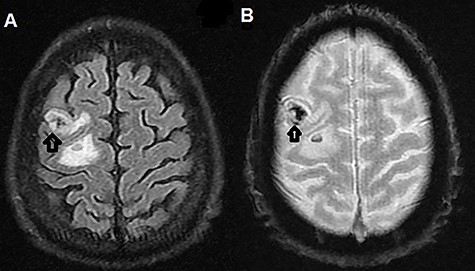

The patient was admitted to the hospital. Brain magnetic resonance imaging (MRI) revealed multiple multifocal hemorrhagic lesions with surrounding edema involving the cerebellum and both cerebral hemispheres, consistent with hemorrhagic metastatic lesions (Figs 1A, B and 2A, B).

(A) T2-weighted MRI axial image showing left parietal isointense lesion with surrounding edema (black arrow); (B) T2-weighted MRI axial gradient echo sequence showing left parietal lesion compatible with hemorrhagic foci (black arrow).